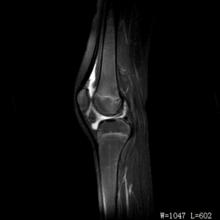

檢查

在髕韌帶與側副韌帶之間,沿關節間隙,有固定而局限的壓痛。麥氏征陽性。研磨試驗陽性。X線檢查有助於排除骨性病變或其它疾患。膝關節鏡檢查的確診率超過90%。